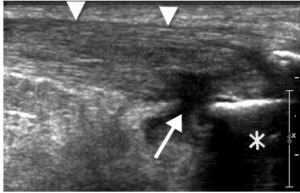

“Common tendon abnormalities include tendinopathy and tendon tears, which impose a substantial cost to society in the United States and abroad. According to the American Public Health Association, tendon disorders account for approximately $850 billion per year in health care costs and indirect lost wage expenditures.4 Accurate and timely diagnosis of musculoskeletal tendon injuries is critical to ensure proper treatment and thus minimize societal costs. Magnetic resonance imaging (MRI) has been the imaging standard for musculoskeletal injuries. However, MRI is costly and overused.5 Improvements in ultrasound technology have made sonography a rapidly growing imaging alternative and complementary tool to MRI for the diagnosis of common tendon injuries.6…..The most defining advantage of sonography over MRI is its real-time imaging capability, which allows for dynamic evaluation of the tendon using a variety of stress maneuvers.16,17 For example, in the neutral position, the long head of the biceps tendon may lie normally in the bicipital groove (Figure 3), only to dislocate medially once the arm, with elbow flexed, is externally rotated (Figure 4). In addition to tendon subluxation, other tendon abnormalities diagnosed dynamically include tendon snapping, friction between two structures such as in shoulder impingement,18 and increasing conspicuity of tendon tears while stressing the tendon or with sonopalpation.17 Real-time dynamic sonographic evaluation provides this unique diagnostic ability using controlled movements.”

..to looking like this:

or like this….

with plenty more examples of it, illustrating how awesome it is and why we should use bedside ultrasound to evaluate tendons more.